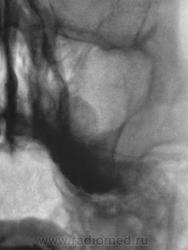

Наши ЛОРики ещё просят боковую проекцию сделать.

Второй случай. уровень слева,субтотальное затенение справа.киста правой половины лобной.....